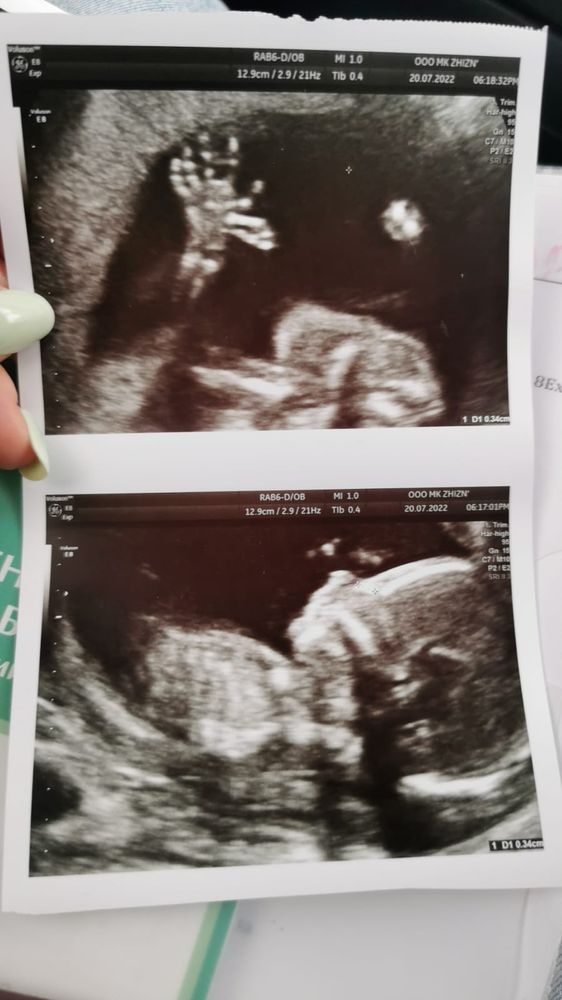

Поскольку на первом скрининге (в 13 и 4) нас напугали гипоплазией носовой кости, я конечно же перезаписалась на повторное, но уже платное УЗИ (провели мы его в 16 недель). По результатам - всё у нас хорошо, носик вырос уже до 3,5 мм. Измерили ТПТ - 2,6 мм - в норму укладываемся. Да, мы проходим по нижней границы нормы по размерам, но врач, посмотрев на мой носик сказала - просто маленький и аккуратный будет как у мамы. Теперь вот с нетерпением жду 2 скрининга, чтобы еще раз померить )

Последнюю неделю болит крестец, поясница, колит и стреляет то там то тут внизу живота. Матка уже поднялась на 7 см от пупка, немного округлилась, шевелений пока не чувствую из-за загиба матки кзади и прикрепления по передней стенке. Врач УЗИ нашел также предлежание плаценты, но успокоила, что у многих на этом сроке она низко и что на 2 скрининге обычно уже все хорошо. Ждем, пока поднимается) Велела стоять в КЛП по 6 раз в день по 1-2 минуте.